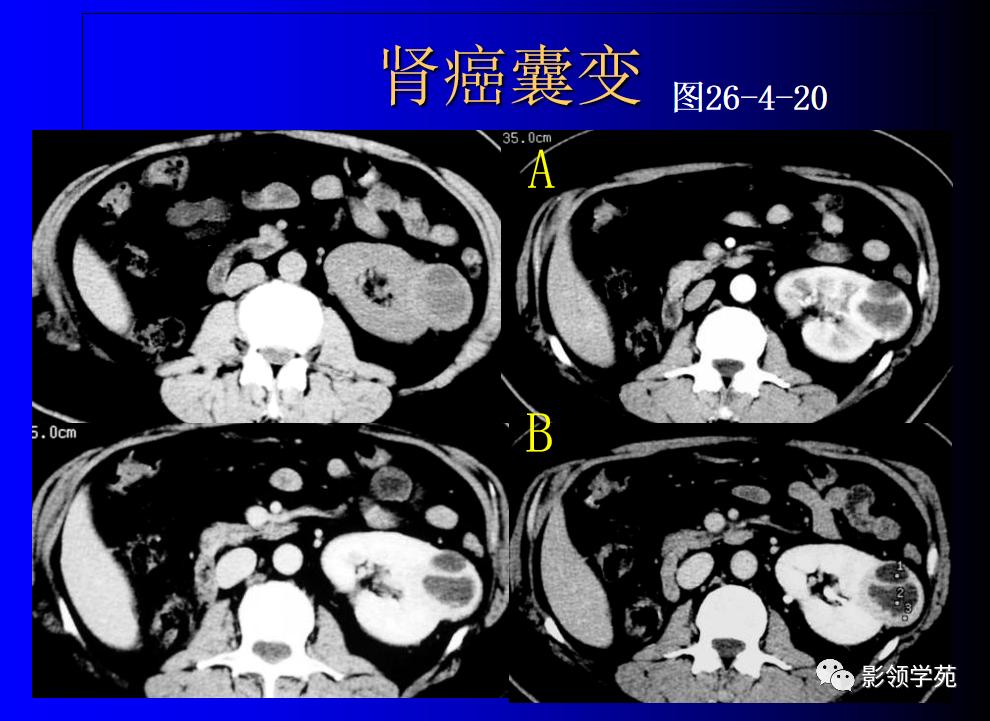

12、肾癌囊变和多房囊性肾癌

肾癌部分囊变易鉴别,少数需和感染性囊肿鉴别。

完全囊变常和肾囊肿混淆,少数不能鉴别。

多房囊性肾癌有完整分隔

1、囊性肾癌的临床及病理

好发于中老年人,约占肾癌的2%~15%。病理组织学可将囊性肾癌分为4种类型:

①单房囊肿性囊性肾癌

②多房囊肿性囊性肾癌

③肾癌囊性坏死

④单纯性肾囊肿恶变。

2、囊性肾癌与肾癌囊变是两个不同的概念

前者是以囊性方式生长为主的肿瘤,后者是实体癌的广泛出血、坏死囊变而成。据Hartman等(1986)统计,囊性肾癌占肾癌总数的10%~15%。囊性肾癌的发病机制总体上还不很清楚,但认为可能是

3、囊性肾癌的CT表现

囊性肾癌的CT表现各异,根据本组影像结果显示,囊性肾癌主要有以下CT表现:

(1)平扫囊内平均CT值较单纯囊肿偏高,约15~20 HU,而单纯囊肿CT值 一般为10 HU以下。

(2)囊壁连续性中断,向邻近肾实质浸润低密度影。

(3)囊壁厚薄不均,有向囊内或囊外凸出的壁结节,可明显强化。

(4)部分囊壁模糊。

(5)平扫囊内密度不均者,增强扫描囊内可出现不均匀强化,CT值可达35 HU左右。

(6)冠状位后重建图像显示为不规则形囊性肿块。

(7)囊壁弥漫弧形钙化,良性单纯囊肿很少见,是否为囊性肾癌的典型征象尚有待商榷。